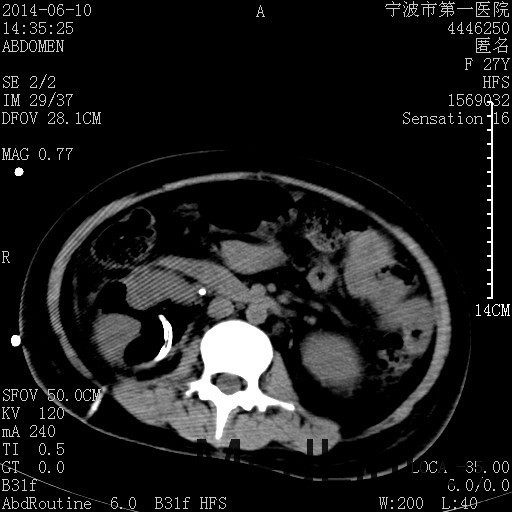

患者,女,27岁,因“右下腹疼痛伴呕吐2天”入院 患者无明显诱因出现右下腹疼痛伴呕吐、发热,体温最高39度,急诊CT示:右肾集气,考虑气性肾盂肾炎。

查体: 右肾区叩击痛,右下腹压痛,无反跳痛。 辅助检查: 空腹血糖9.7mmo/L,餐后血糖18mmol/L 血常规:白细胞 11.3*109/L, 中性百分比 77.4%, 血红蛋白 8g/L, 血小板 319*109/L 尿常规 WBC+++ 生化:白蛋白 37.5g/L,肝肾功能正常 泌尿系CT:右肾集气

诊断为“气性肾盂肾炎,感染性休克,糖尿病酮症酸中毒” 血、尿、脓液培养均示“克雷伯杆菌” 入院第2天行“右双J管置入术” 入院第3天、7天行“右肾穿刺造瘘术” 入院1月行“右肾切除术” 术后顺利康复出院。